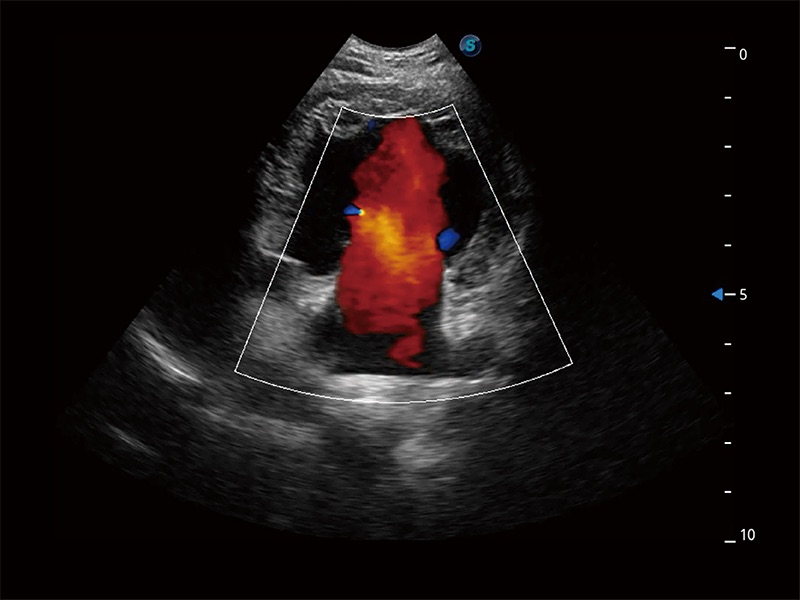

ProPet 80 配备了丰富的心脏探头群、先进的成像技术和专业的心脏测量工具,可帮助动物医生为不同体型和生理结构的动物提供心脏和心肌功能的全面评估。

实时用颜色表示心肌组织运动,观察和定量组织的运动情況,对快速检测与评估心肌的灌注和活性、电传导及心肌收缩和舒张功能等均能提供重要的诊断信息。

通过心肌识别技术与二维斑点追踪技术相结合,对心脏的超声图像进行量化分析。计算心肌17个节段的应变、应变率、速度、位移等,并通过牛眼图的形式进行呈现。

通过360度任意调节3条M型取样线,在同一心动周期上观察心脏不同位置的运动曲线,得到准确的心功能测量数据,有效评估心肌运动及左心室功能。